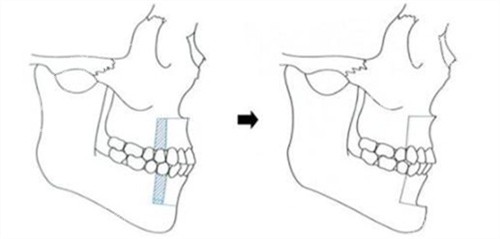

牵张成骨术,是一种内源性骨组织工程技术,通过外科手段将骨骼切开,在切骨线两侧安装特制的牵张器,经过一定的延迟期后,缓慢牵张切骨间隙,使间隙不断增宽,并激发机体组织再生的潜力,在牵张间隙内不断形成新生骨组织。同时,该技术还能使骨骼周围的肌肉、神经、血管、皮肤等软组织同期延长,从而达到延长骨骼、改善形态的目的。

软组织同期延长:牵张成骨术不仅可以延长骨骼,还能使骨骼周围的肌肉、神经、血管、皮肤等软组织同期延长,确保术后形态的和谐与美观。

提高术后稳定性:通过牵张成骨术形成的骨组织更加坚固稳定,有助于减少术后畸形复发的风险。